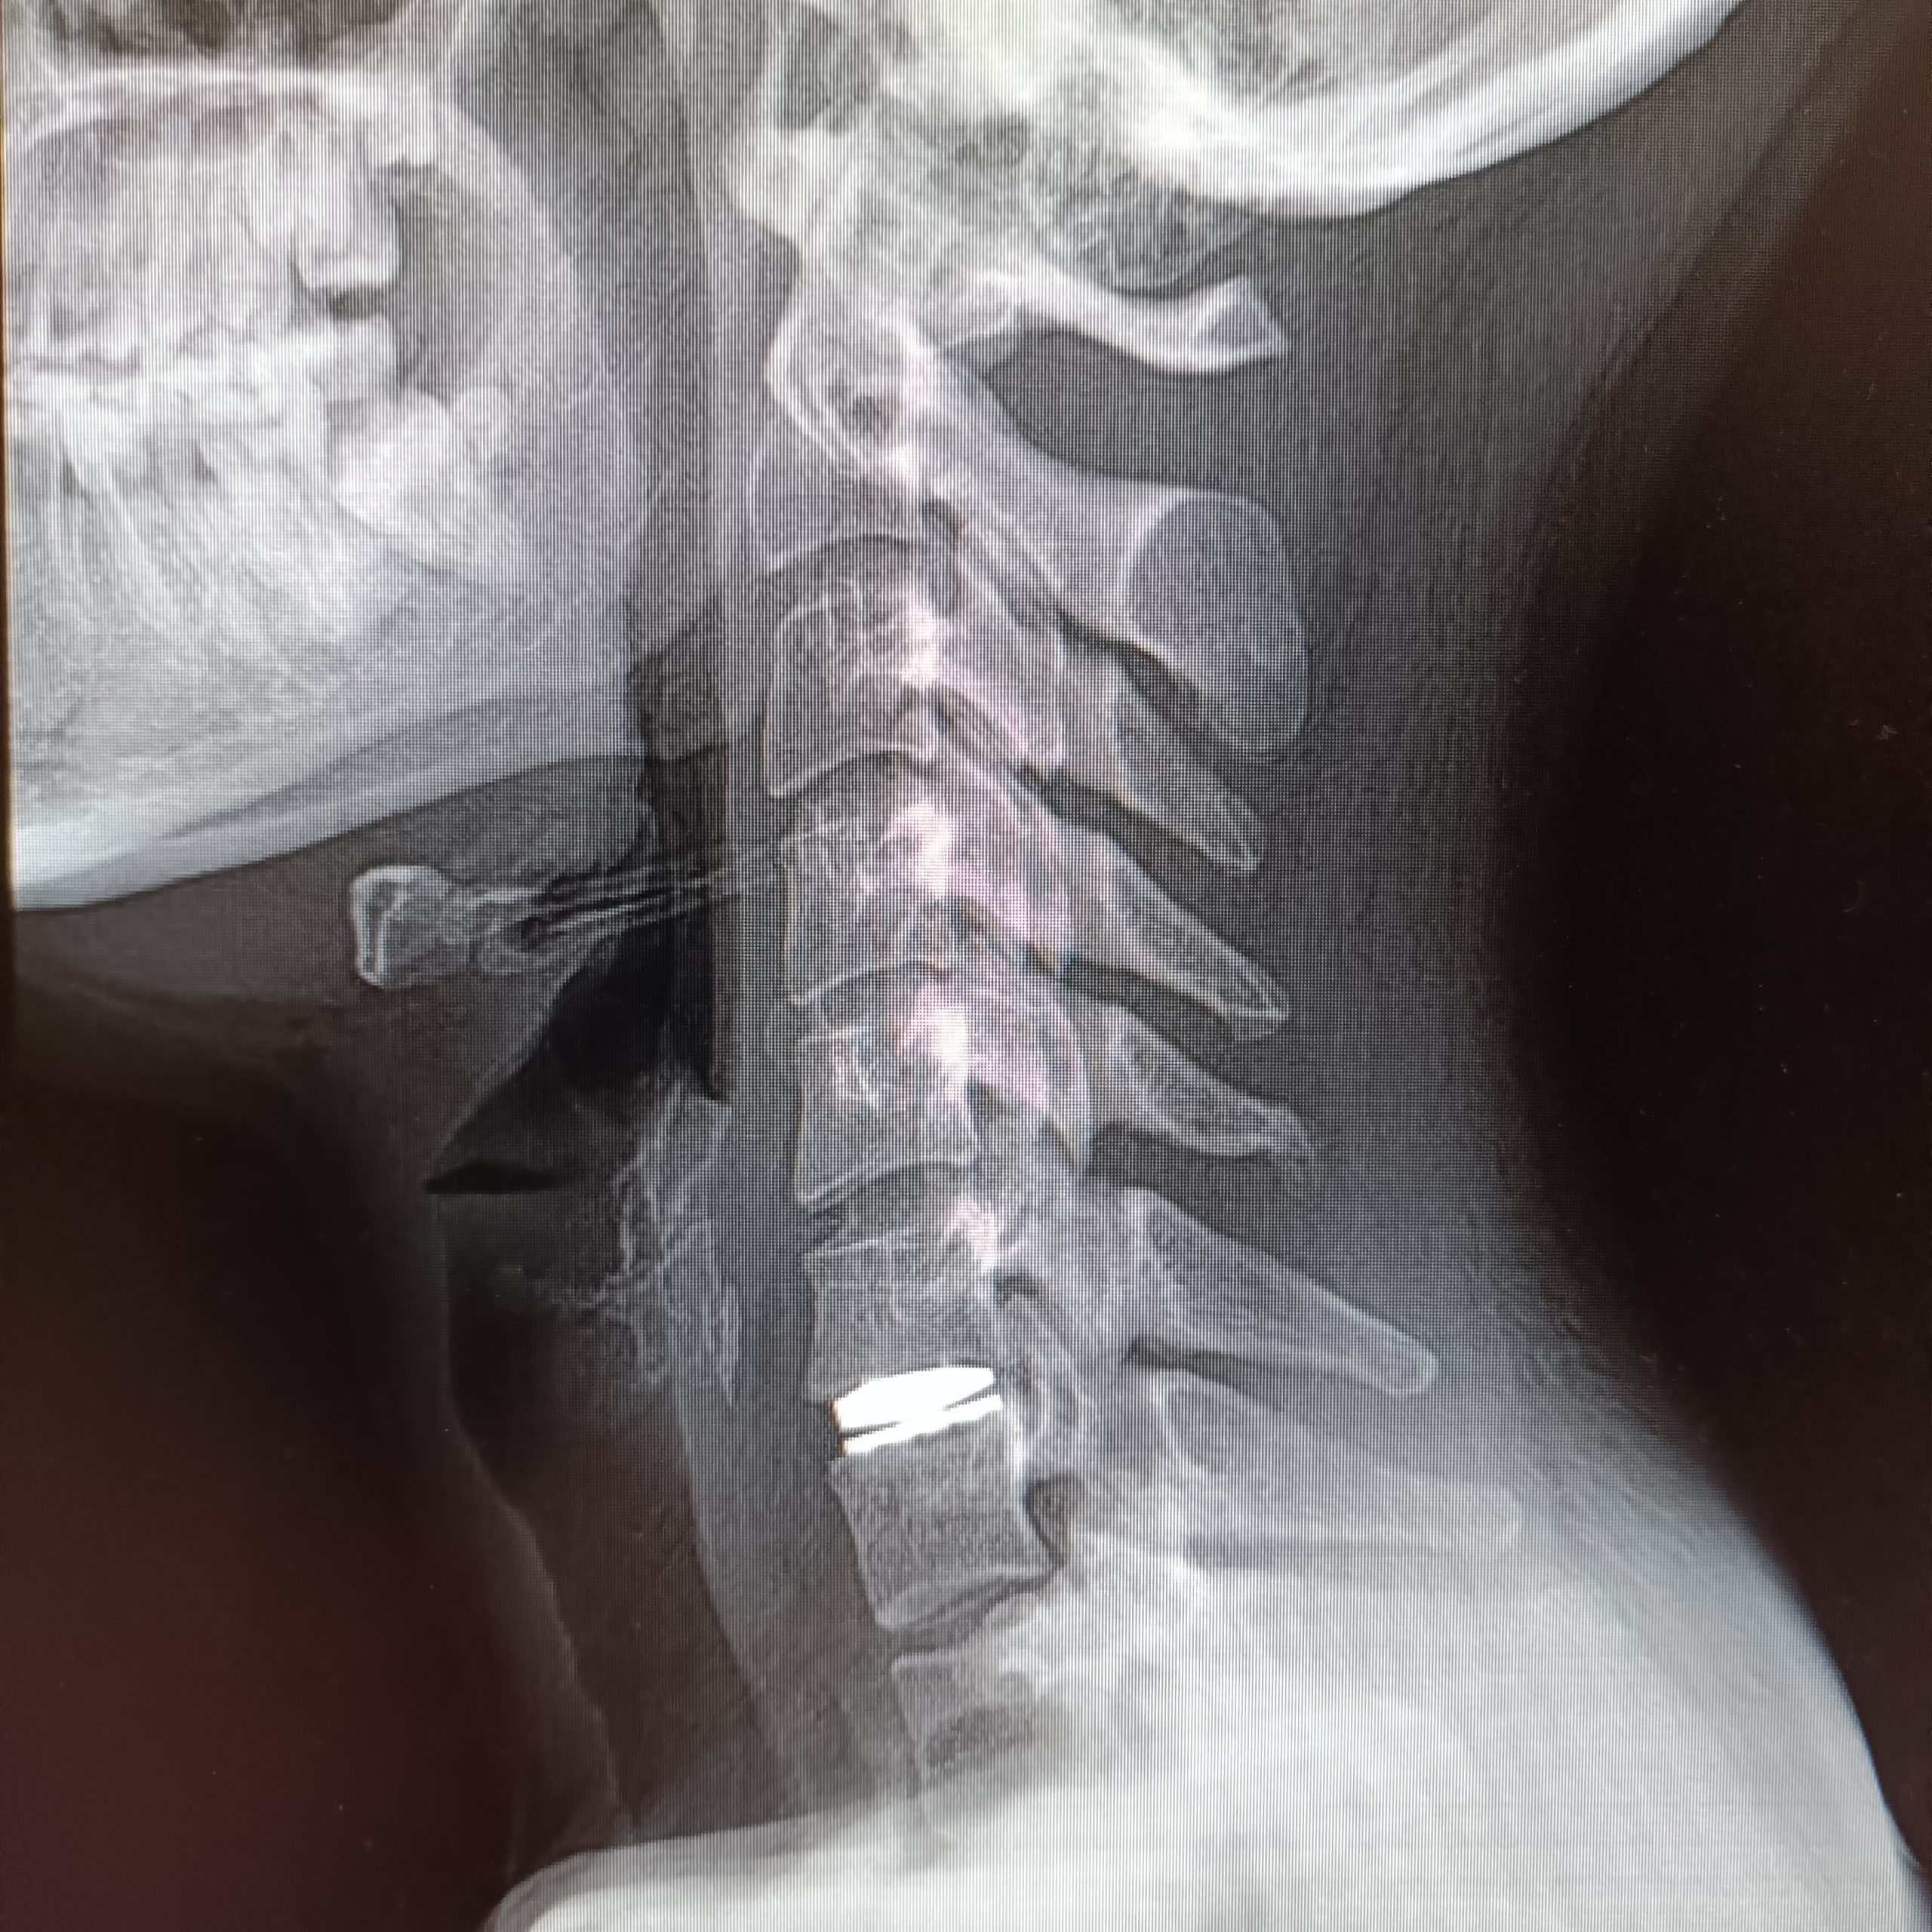

Servikal Disk Protezi

Günümüzde boyun fıtığı cerrahisinde hem erken dönemde hareket kabiliyetinin kısıtlanmadan en doğal şekliyle korunması hem de söz ettiğimiz “komşu segment hastalığı”nın önlenmesi açısından tercih edilen yöntem servikal disk protezleri. Bu protezler vücudun kabul ettiği, herhangi bir alerjik reaksiyon yaratmayan özel plastik ve seramik alaşımlar ile titanyum gibi hafif ve çok dayanıklı malzemelerden üretiliyor.

Yeditepe Üniversitesi Koşuyolu Hastanesi’nde servikal disk protezi kullanılarak başarı oranı yüksek boyun fıtığı ameliyatları yapıyor. Hastalar ameliyat sonrası en kısa zamanda sağlıklarına kavuşup günlük hayatlarına dönme fırsatı buluyor. Ayrıca boynun kendi doğal hareketlerini, esnekliğini ve yük taşıma kapasitesini koruyan servikal disk proteziyle yapılan ameliyatlarla tedavi edilen bölgenin alt ve üstündeki disklerin sağlığı da korunmuş oluyor.

Boyun fıtığını gidermek için kullanılan disk protezinin yerleştirilmesi, 1-1.5 saatlik bir ameliyatla tamamlanıyor. Hastalar genellikle sadece bir gün hastanede kalıp ertesi gün taburcu oluyor. Ameliyat sonrasındaki ilk 1-2 hafta içinde hastaların dinlenmeleri ve sert boyun hareketlerinden kaçınmaları öneriliyor. Sonrasında hasta hiçbir kısıtlama olmadan normal günlük yaşam ve aktivitelerine geri dönüyor. Ameliyat sonrasındaki erken dönemde bile boyun hareketlerinin kısıtlanmasına gerek olmadığı için diğer cerrahi yöntemlerden sonra sıklıkla kullanılan sert boyun korsesine de ihtiyaç kalmıyor. Bu da hastalar için ek bir konfor ve kolaylık demek.

Servikal disk protezi kalıcı ve dayanıklı, bu yüzden ileride çıkarılması ya da değiştirilmesi gerekmiyor. Boynun doğal hareketlerini bozmadığı ve diğer sağlıklı diskleri koruduğu için de hasta açısından günlük hayatta hiçbir kısıtlamaya neden olmuyor.